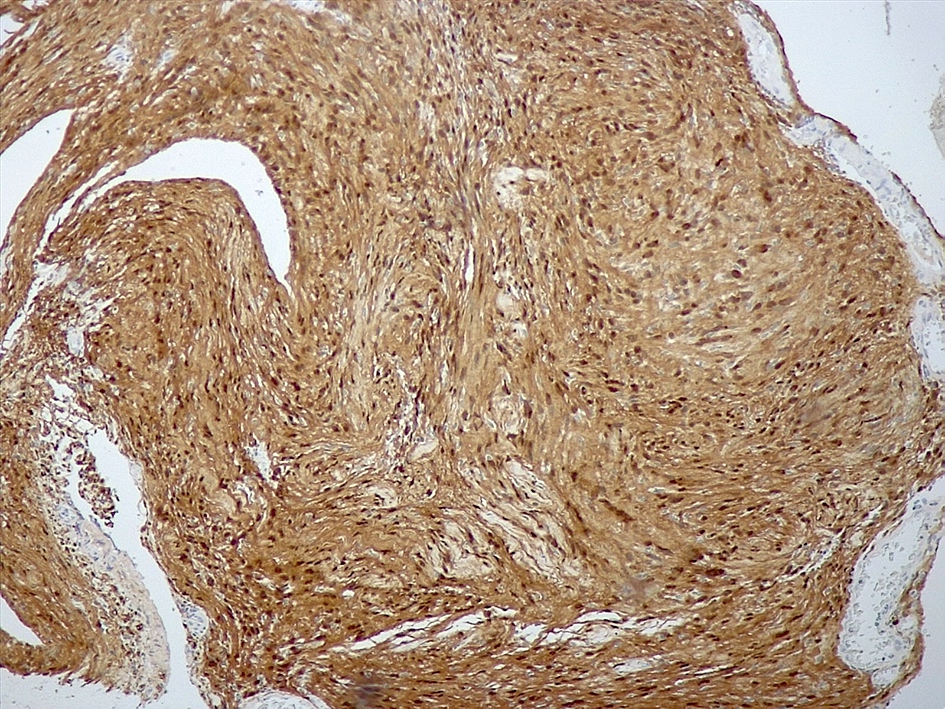

Positive stains

- Strong diffuse SOX10 (Am J Surg Pathol 2008;32:1291)

- Strong diffuse S100 (Appl Immunohistochem Mol Morphol 2012;20:445)

- Neurofilament stain demonstrates axons predominantly pushed to the periphery of the tumor